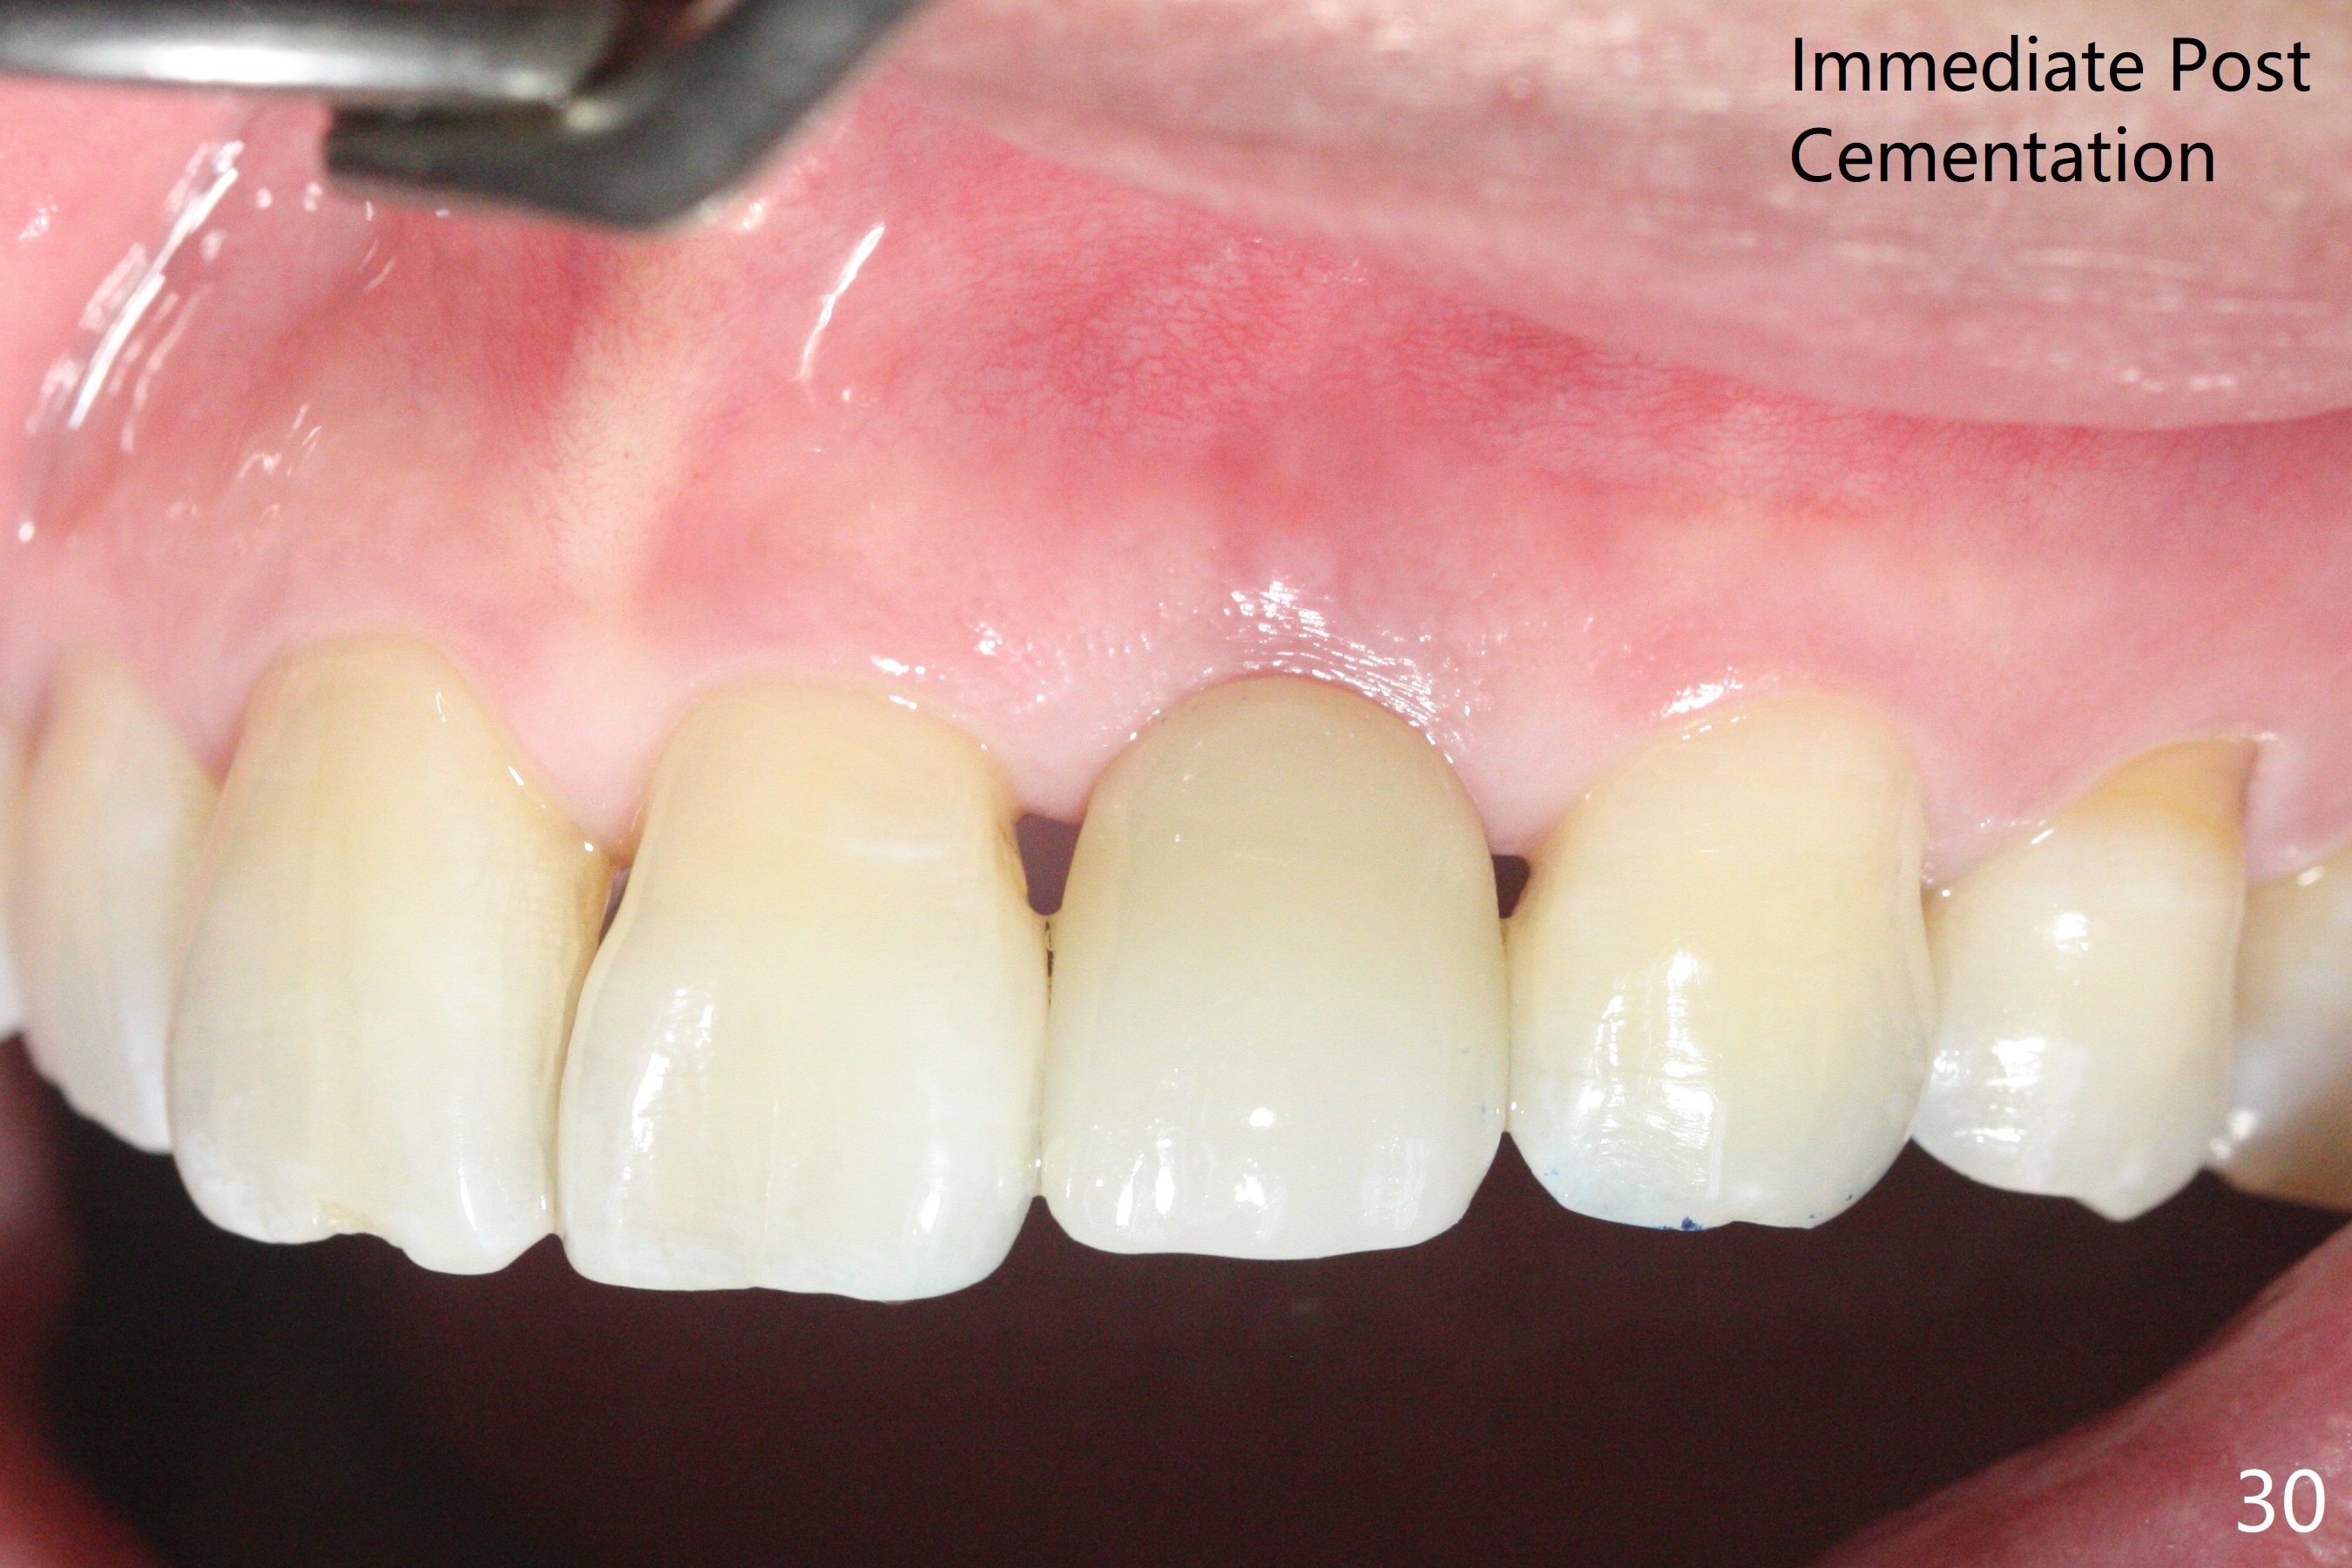

病人回来带来瘘道(图一),不过不会增加难度,病牙去除,它便自动消失。尽管颊侧骨壁完全失去,颊侧牙龈仍丰满(图二),为什么呢?第一,因为粗大牙根存在,第二两旁牙齿,牙槽骨撑着帐篷(侧切牙颊侧牙龈),第三,牙冠。为了防止术后牙龈塌陷,尽量不切开,即刻放置植体(牙根);由于前牙缘故,这次植体不能很大,所以植骨必须过度(over grafting),最后即刻制作临时牙冠,撑住牙龈。这就是所谓每个人进入角色。这个牙根有一种先天性畸形:dens in dent (图三(腭侧观):箭头)。尽管腭侧牙根畸形,腭侧骨壁吸收临床上并不严重,所以钻洞仍偏腭侧。当预定最后钻头还在钻洞时,填入大量粘性骨块(图四:*),细长植体还没有完全卡入鼻底(图五),最后好像可以(图六,七)。植体,骨粉入位(图八),最后临时牙冠出场(图九)。尽管植体小,术后一周临时牙冠仍然可以维持牙龈原有形状(emergency profile,图十:箭头(*:树脂强化牙冠固定))。图十一以不同角度显示瘘道缩小。术后三周取出有些松动的临时牙冠,骨粉虽然还没有被肉芽组织整合,但是显得正常,周围牙龈健康(图十二)。术后4个月牙龈形态正常(图十三),没有触痛;颊侧骨板轻度凹陷(图十四);骨粉仍在原位(图十五)。术后7个月骨粉仍在原位(图十五,十六,但是冠部密度减低(可能骨粉流失,需要牙周或者树脂敷料保护)),没有螺纹暴露。但是牙冠边缘暴露,说明牙龈收缩(图十七,与图十三对比),颊侧骨板仍塌陷(图十八)。插入龈线取得多个目的:修整基台边缘,取模,颊侧牙龈推向颊侧,有利于即将衬里牙冠龈缘进入龈下(图十九)。取模后牙冠边缘(图二十:<)衬里,然后修整,变窄,以便插入龈下,促进颊侧牙龈下降(图二十一,二十二)。术后8个月牙冠粘固前牙龈健康(图二十七,八),牙冠(图二十九)固位后,病人满意(图三十),咬合调整(图三十一),注意腭侧粘固粉流出通道(<)。